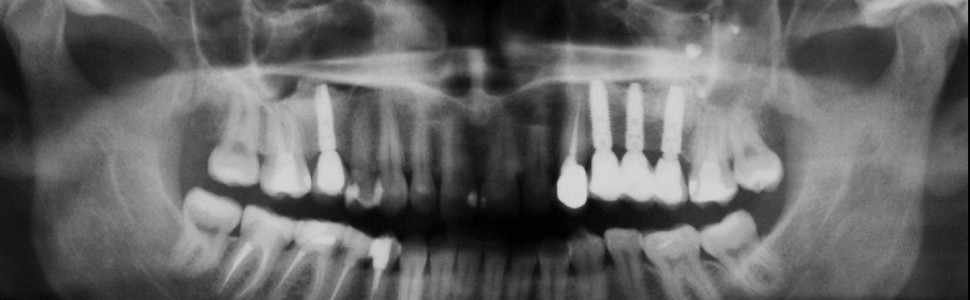

W artykule przestawiono istotne zagadnienia dotyczące anatomii zatoki szczękowej, które mogą mieć wpływ na przebieg zabiegów chirurgicznych i ewentualne powikłania. Szczegółowo opisano techniki podniesienia dna zatoki metodą zamkniętą i otwartą oraz ich skuteczność. Przedstawiono rodzaje materiałów stosowanych do augmentacji dna zatoki. Omówiono również alternatywne rozwiązania implantologiczne, takie jak podniesienie dna zatoki szczękowej bez użycia materiałów wypełniających oraz zastosowanie wszczepów jarzmowych.

The article describes significant aspects regarding the anatomy of the maxillary sinus that may have an influence on the outcome of surgical procedures and on possible complications. In particular there is a description of the technique of lifting the floor of the sinus using closed and open techniques and their effectiveness. There is a presentation of the types of grafting material used for augmentation of the floor of the sinus. There is also a discussion of alternative solutions using implants, such as the lifting of the sinus floor without the use of grafting materials and with the use of zygomatic implants.